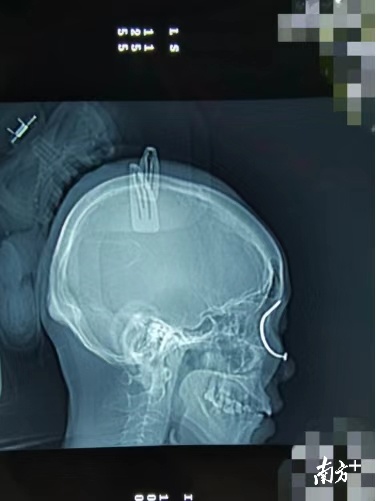

接诊的医生是市二医院的副主任医师沈沛阳博士和住院总医师叶祖科。他们回忆说,患者是从外院转来的,入院时,一颗又粗又长还生了锈的铁钉从患者的左眼角下端插入,斜行穿过左眼球,再从对角左眉弓处穿出。简单说,这颗铁钉是在患者左眼眶里转了个弯。医生检查后表示,裂隙灯下,患者的左眼已经出现了玻璃体脱出、创伤性视网膜裂孔、虹膜裂伤、结膜裂伤、眼睑裂伤等表现。外院CT提示左侧上额窦区金属钉异物存留、上穿,可能累及眼眶。医生表示,情况十分危急,必须马上进行手术。

当夜,眼外伤团队在全麻下为患者进行了多项手术,包括:“左眼眼球异物去除术;左眼巩膜探查术;左眼巩膜裂伤缝合术;左眼玻璃体药物注射治疗;左眼结膜缝合术;左眼眼睑裂伤缝合术”。经过医护人员们熬夜奋战,最终成功取出了一枚长约8cm的生锈铁钉,也保住了患者的左眼球。